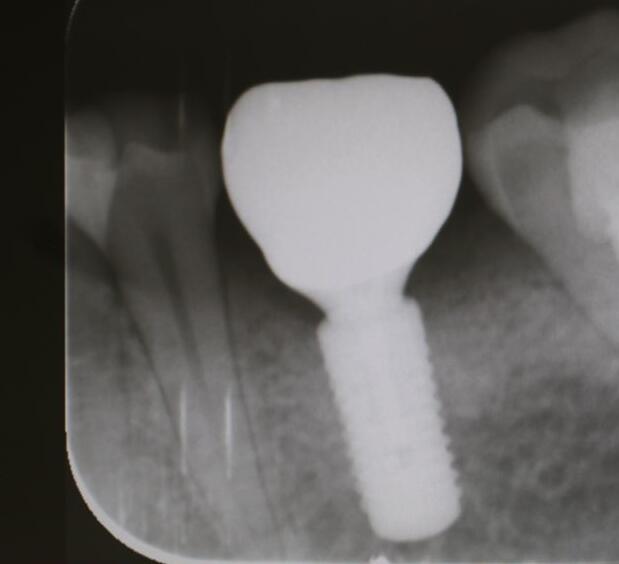

牙齒種植是指在牙槽骨內(nèi)植入人工牙根,待人工牙根成活之后,就能夠在其上連接入基臺(tái)和義齒。能夠仿真牙的果,并且其療也是理想的,因此很多人都稱(chēng)他為人類(lèi)的第3副牙齒 。種植牙的維持時(shí)間一般在10-20年左右,果好。